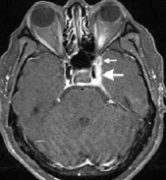

Tolosa-Hunt综合征患者左侧额部疼痛、左眼睑下垂、复视来诊。MRI检查有助于明确病变部位及累及组织的范围。(3)肿瘤转移:很多肿瘤可以侵犯海绵窦:脑膜瘤、听神经瘤、脊索瘤、鼻...